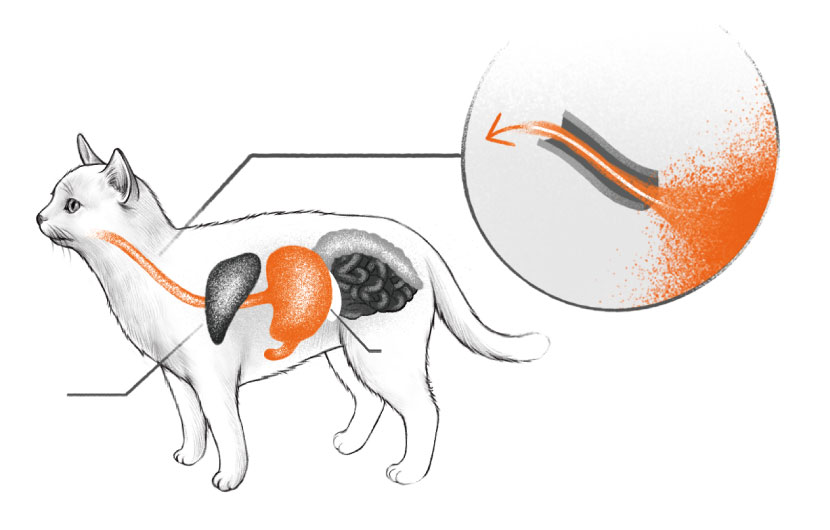

식도 내 이물이 섭취되었다면, 내시경 검사를 통해 이물의 위치와 크기 등을 확인합니다.

소화되지 않는 음식물 등을 섭취했거나 반려동물이 구토를 한다면!

이물의 표면이 매끈하고 크기가 작아서 식도를 통과할 때 식도벽 손상 위험이 적어 내시경을 통해 제거가 가능합니다.

반면 식도 내 손상이 될 위험이 있다면, 이물을 위 안으로 밀어 넣어 위 절개술로 제거하게 됩니다.